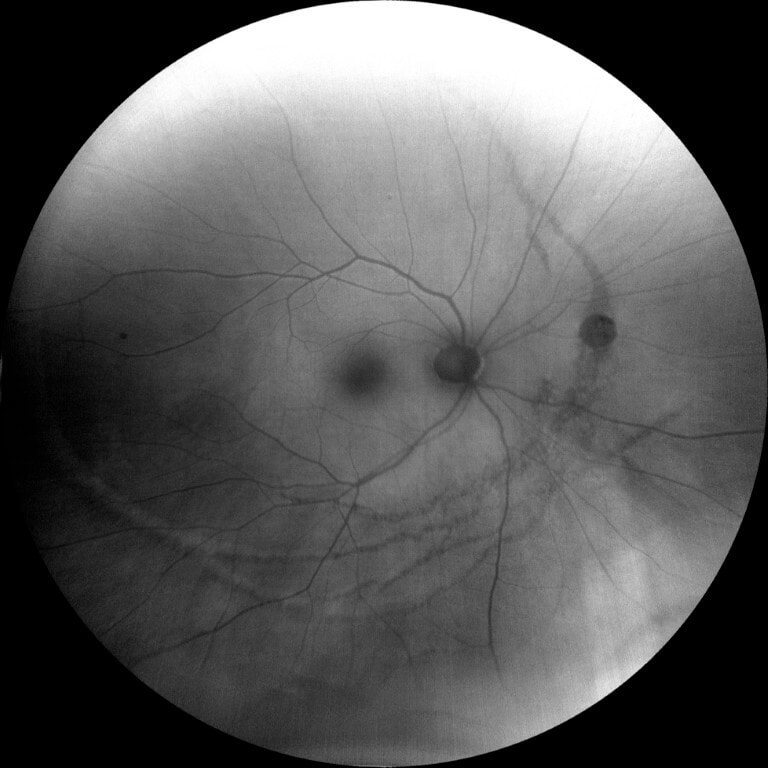

A 67-year-old male presented for a routine eye exam. The patient reported no visual complaints and denied ocular pain, photopsia, new floaters, metamorphopsia, or diplopia. His medical history included obesity and no history of systemic inflammatory or infectious disease. He denied any history of ocular trauma or surgery. The patient’s uncorrected and corrected visual acuity was 20/20 in each eye. Extraocular muscles, confrontation fields and pupils were normal. Slit-lamp examination for the right and left eye was unremarkable. Following dilation with 1% tropicamide and 2.5% phenylephrine, funduscopic examination was performed. The optic discs were normal with a cup-to-disc ratio 0.30 round. The macula in each eye was flat with normal OCT (Figure 1-2). However, examination of both eyes revealed multiple, curvilinear, pigmented chorioretinal lines originating in the posterior pole and extending outward in a distinct spiral pattern toward the midperiphery. Color fundus photographs as well as fundus autofluorescence images were obtained (Figures 3-6). There was also a punched-out chorioretinal lesion nasal to the optic nerve head in the right eye (Figure 3,5).

Figure 5: Fundus autofluorescence of the right eye showed mixed areas of hypo- and hyperautofluorescent lines corresponding to RPE atrophy and hyperplasia, with a hypoautofluorescent area nasal to the optic nerve head consistent with an inactive punched-out lesion.